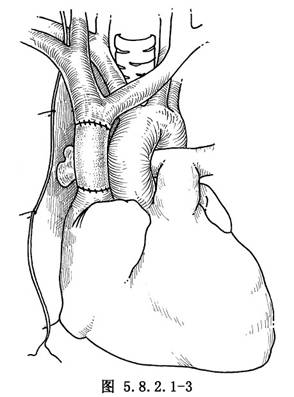

5.切除上腔靜脈前,先解剖和遊離阻塞段上腔靜脈的近心端(上腔-右房接合點)和遠心端(左、右無名靜脈的匯合處),然後各置一把Potts鉗(圖5.8.2.1-1)。

6.上腔靜脈切除後,用18或20號的聚四氟乙烯(PTFE)人造血管與上腔靜脈吻合。先吻合遠心端,用5-0的Prolene線,在上腔靜脈的遠端和人造血管之間縫兩條牽引線,結紮後用連續外翻縫合法,分別縫合前、後壁,打結在血管外面。同樣的方式,吻合近心端(圖5.8.2.1-2)。近心端縫線未打結前,向移置血管內注入肝素鹽水沖洗,然後放開遠端Potts鉗,排淨移置血管內所有空氣,最後移去近端阻斷鉗(圖5.8.2.1-3)。